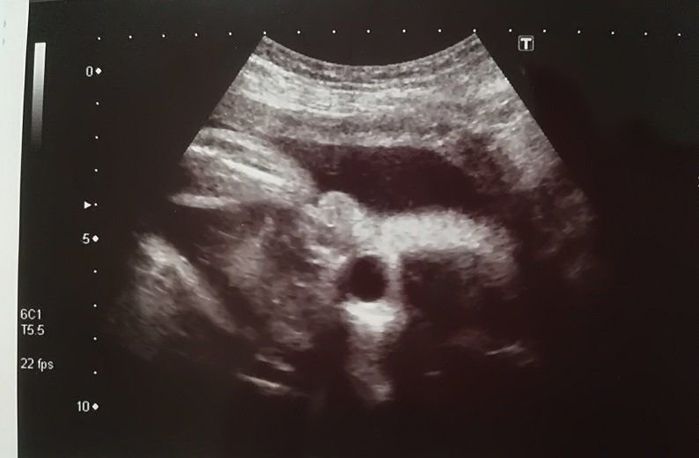

妊娠9週目のエコー写真

「もう、人の形をしている!」と驚きました。妊娠と同時に、里帰り先の産院を予約しました。その喜びをすべて吹っ飛ばしたのが、“つわり”。程度は違うものの皆さん経験するようですが、私は、家のビニール袋がすべてなくなるまで吐いてしまうという重症でした。内科で毎日点滴を受けながら乗り切り「母が食べられなくても、赤ちゃんて育つものだなぁ」と、感心しながら健診を受けていました。